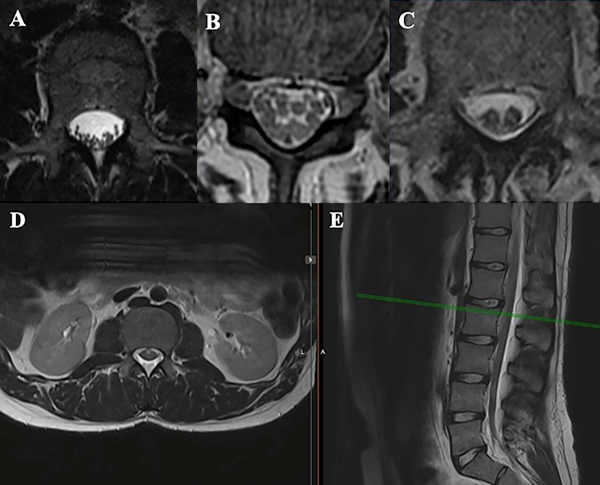

En RMN pueden verse 3 patrones diferentes6,7:

Otros hallazgos en RMN son aglutinación y/o engrosamiento de raíces nerviosas y formación de quistes aracnoidales (Figura 6).

Figura 6: Imágenes de RMN lumbar en secuencia T2, a nivel L2. A- Configuración habitual del canal medular a nivel lumbosacro, se visualizan múltiples raíces nerviosas. A este nivel las raíces de la cola de caballo se ubican en el saco tecal a nivel dorsal, debido al efecto de la gravedad en el decúbito del paciente; B y C- Aglutinación y distribución irregular de raíces nerviosas, hallazgo característico de la aracnoiditis adhesiva; D y E- Imágenes de RMN de la paciente presentada, donde se observa aglutinación y engrosamiento de raíces nerviosas.